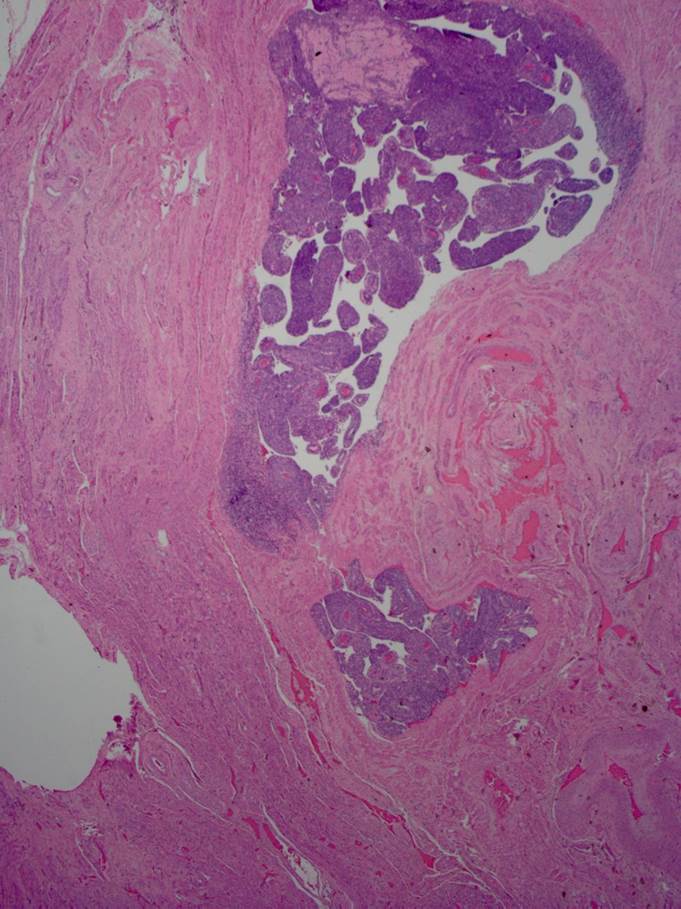

A 28 year old male presents with gross hematuria after a trip abroad. Cystoscopy and...